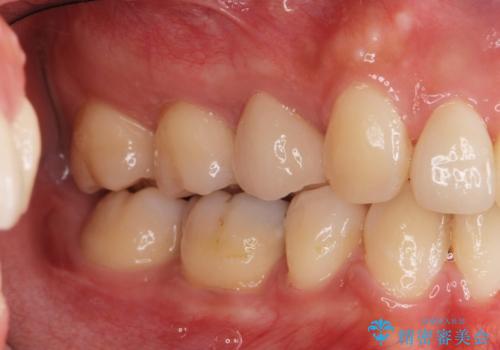

- 右上の5番目の歯の神経の治療のやり直しとセラミック治療を行いました。

途中矯正治療を挟んでいるため、少し歯並びがかわっています。

術前はCRで蓋をしてあるだけでしたが、クラウンにした方が破折のリスクが少なくなります。また、根の治療がしてある歯ですが、クラウンにした方が封鎖は確実なため、長期的には有利です。また、変色の進行も外からは見えなくなりますので審美的です。